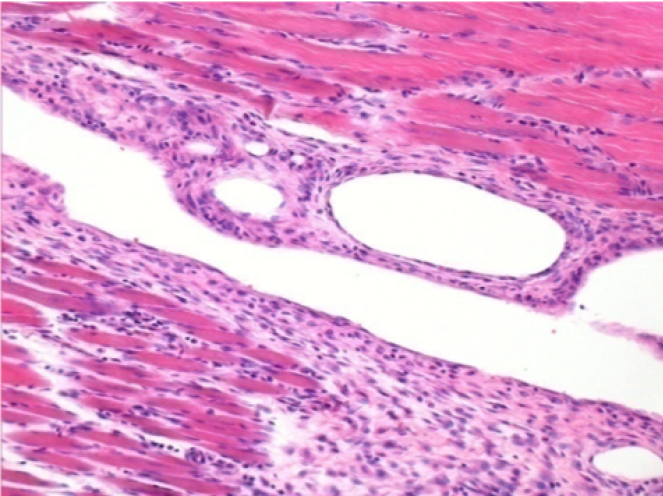

1 mes después de la inyección de Endopeel 0,1 ml en el músculo pretibial derecho.

¡Lo que se ve en negro en las imágenes no es una necrosis como podrían imaginar algunos científicos!

De hecho, hay que tener en cuenta 4 conclusiones

08